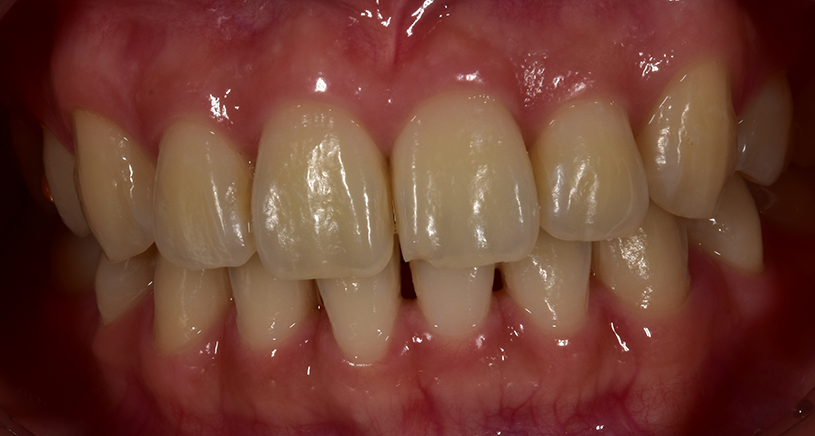

< 사례 1 >

블랙트라이앵글 무삭제라미네이트 <블랙필름> 치료 전

블랙트라이앵글 무삭제라미네이트 <블랙필름> 치료 후